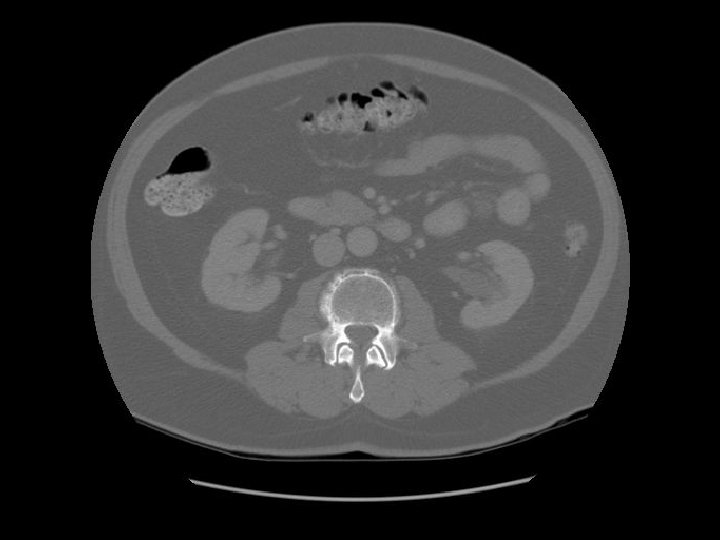

Kidney Right Kidney

Descending colon Right

Renal pelvis

Ascending colon Right colon with fecal material.

Abdominal aorta about to bifurcate.